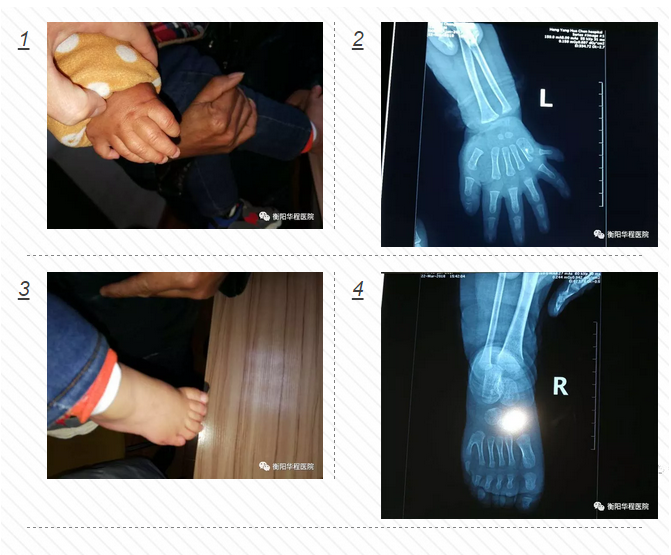

面對這位只有1歲的小患者,骨科中心醫(yī)護人員進行了一番細(xì)致檢查。尹治華醫(yī)生發(fā)現(xiàn)小城城的“多指”情況并不是特別復(fù)雜,突出的關(guān)節(jié)部位并沒有長出骨頭,只需切除多出的指頭,再將表皮重新縫合,扎死血管和神經(jīng)就可以了。“孩子太過幼小,血管和神經(jīng)均很纖細(xì),需借助顯微成像技術(shù)完成手術(shù)。而留下的疤痕組織也會在成長過程中逐漸減淡。”骨科中心尹治華醫(yī)生表示。3月23日小城城在全麻下行雙側(cè)多指、多趾切除功能重建術(shù),經(jīng)過一個小多小時的焦急等待,孩子平安從手術(shù)室里出來了,手術(shù)非常成功,小城城媽媽那顆懸著的心終于著了地。

尹治華醫(yī)生介紹,多指這種先天畸形約占先天性上肢畸形的39.9%,其發(fā)生率約為1%;男性高于女性,男女患病比例為3∶2;右手多于左手,比例為2∶1,雙手發(fā)病約占10%,這其中拇指多指發(fā)病率約占總數(shù)的90%以上。究其原因,主要與遺傳有關(guān),但也不排除環(huán)境因素的影響。據(jù)了解,孩子的父母、親屬中并沒未出現(xiàn)過多指癥狀,推斷與環(huán)境因素有關(guān)。

” 一般來說,孩子3至6個月大時為最佳手術(shù)年齡,因為這個時間段孩子生長發(fā)育、組織愈合較快,骨折、關(guān)節(jié)脫位、畸形易于矯正。” 尹醫(yī)生說,像小城城這種并指畸形雙側(cè)同發(fā),他的多生手指僅以狹小的線狀皮蒂和正常手指相連,是任何時候都可以施行手術(shù)切除的,但如果孩子是屬于多生手指有指甲、骨關(guān)節(jié)、肌腱和神經(jīng)血管束與正常手指相連,就需施行關(guān)節(jié)囊、肌腱等較復(fù)雜的手術(shù),我們會建議家長推遲到孩子學(xué)齡前施行手術(shù); 如果要行骨關(guān)節(jié)矩形手術(shù)的,我們會建議在12歲以后。